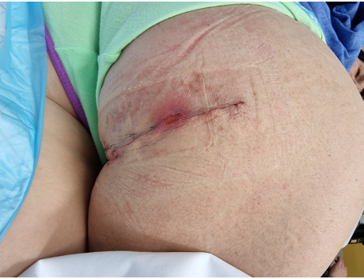

Postoperative infection

Incision

- longitudinal incision - better for retracted or chronic injury, find and protect sciatic nerve distally

- horizontal incisions - can use in more acute setting